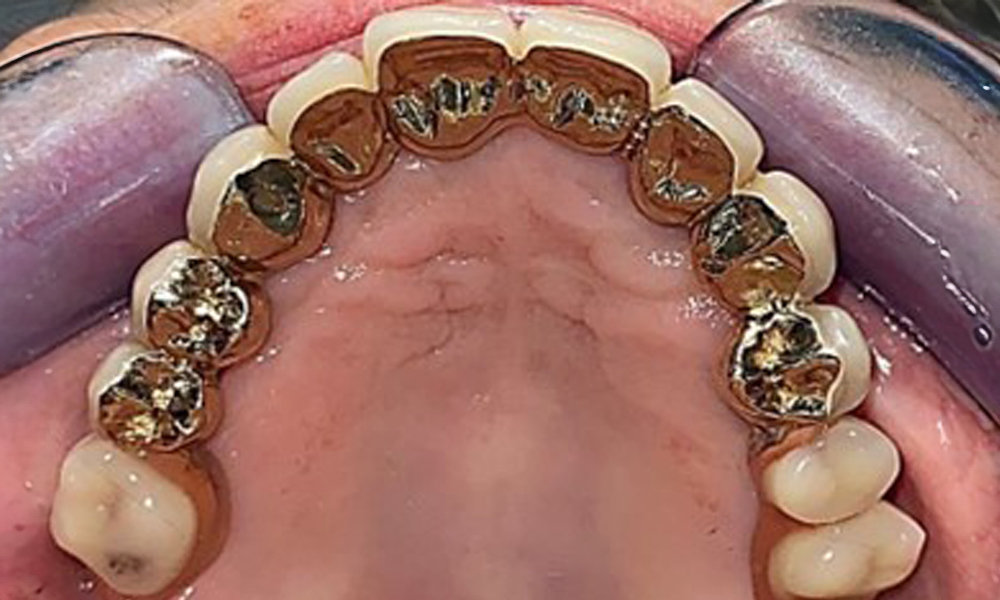

The patient was fitted with a combined removable maxillary telescopic prosthesis more than 25 years ago (Fig. 1, Fig. 2, Fig. 3) and is very happy with her dentures. The patient has an adequate fixed denture for the mandible (Fig. 4).

Occlusal view: Maxilla with removable, palateless denture.

Fig. 3: Occlusal view: Maxilla with removable, palateless denture.